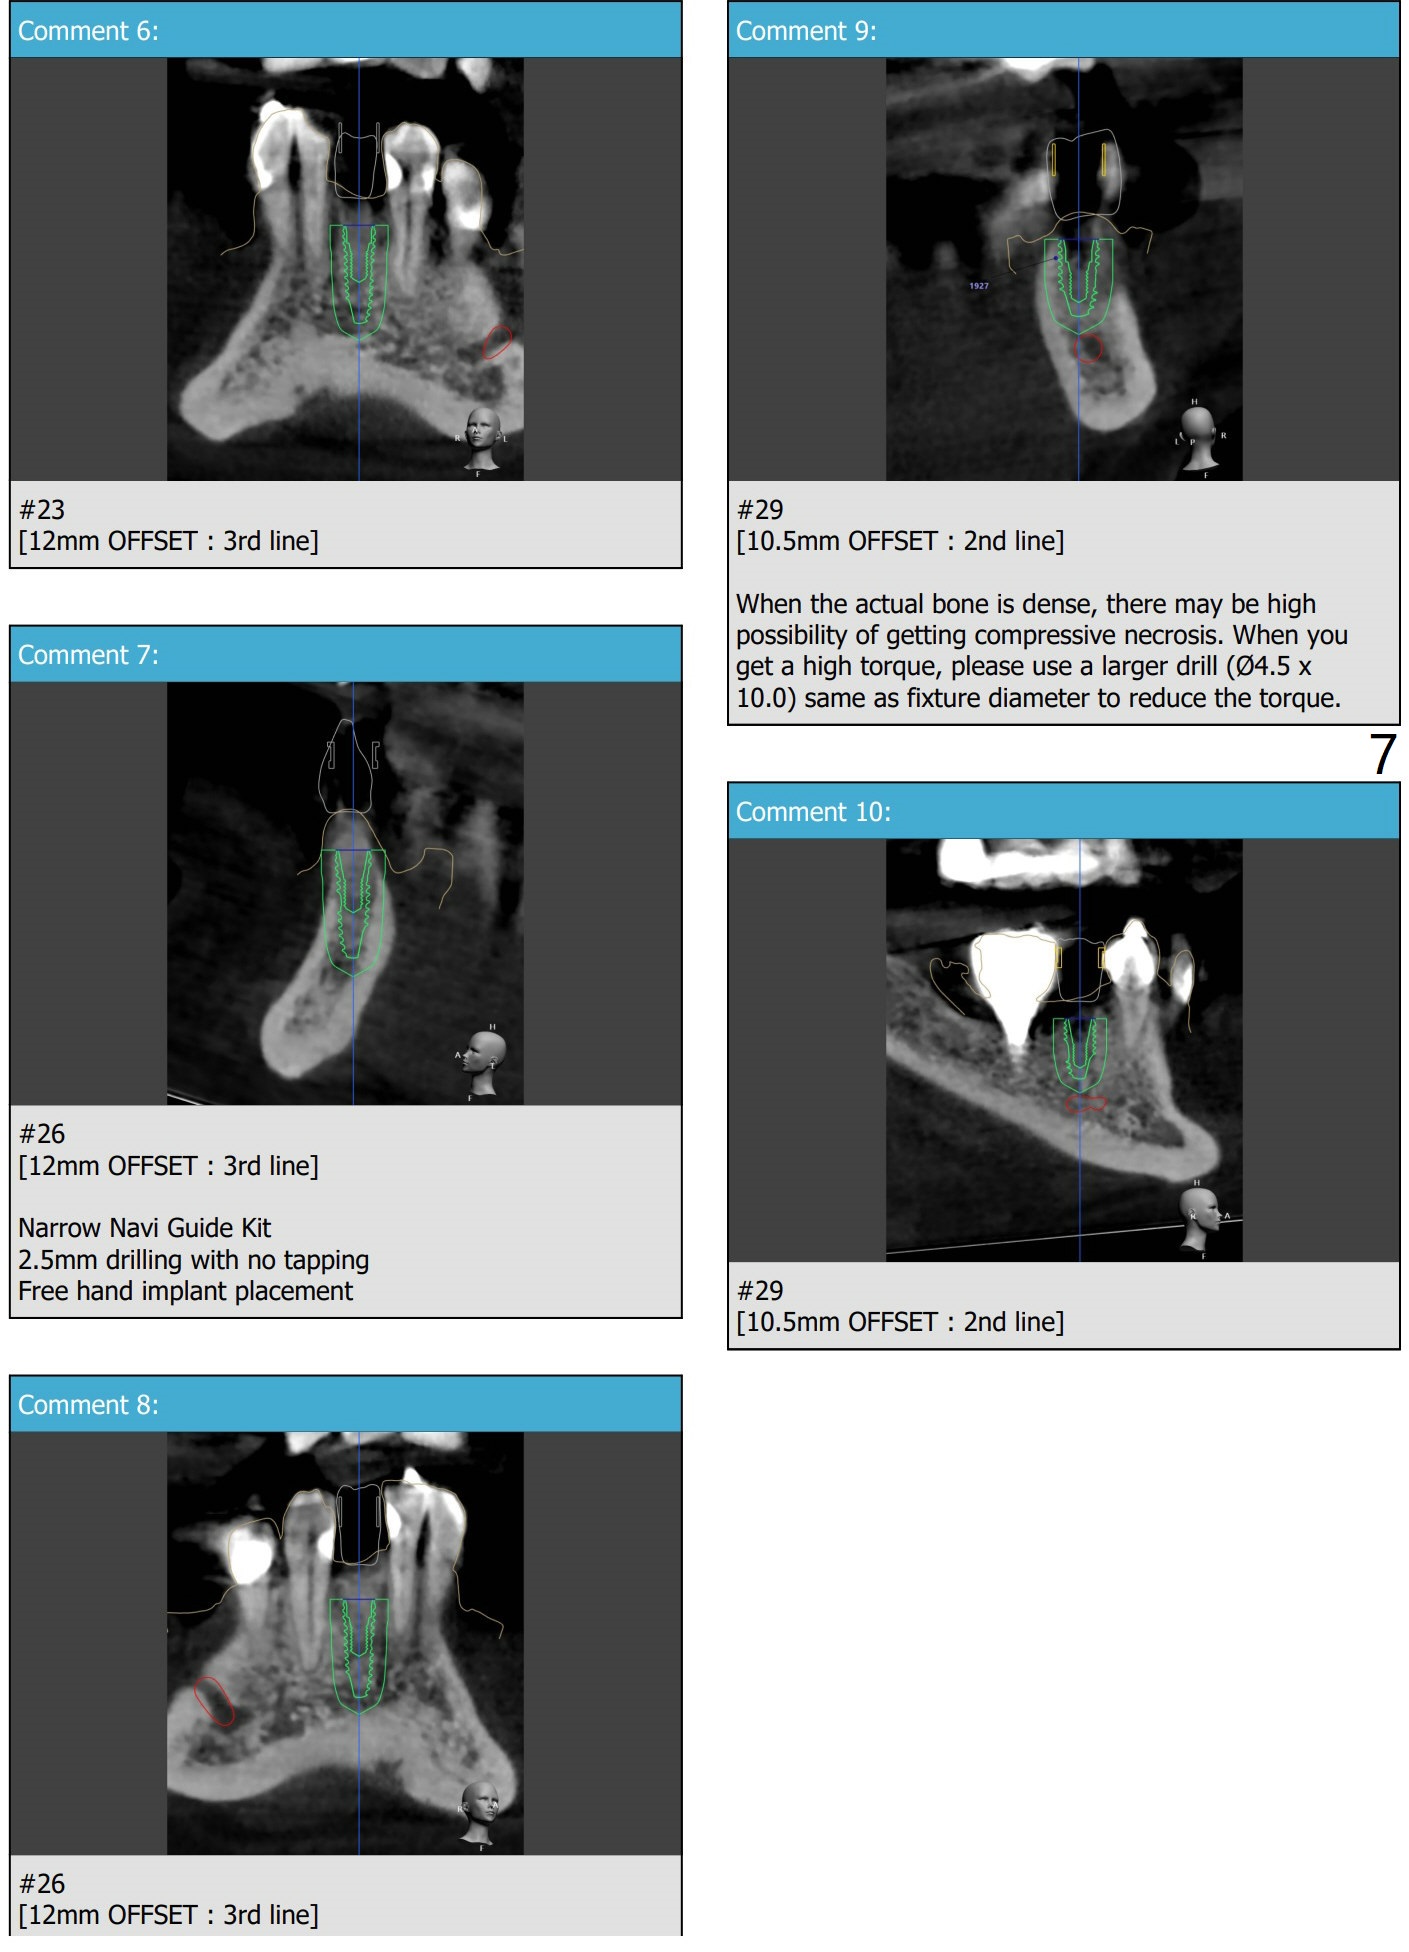

导板钻洞徒手植入

57岁女